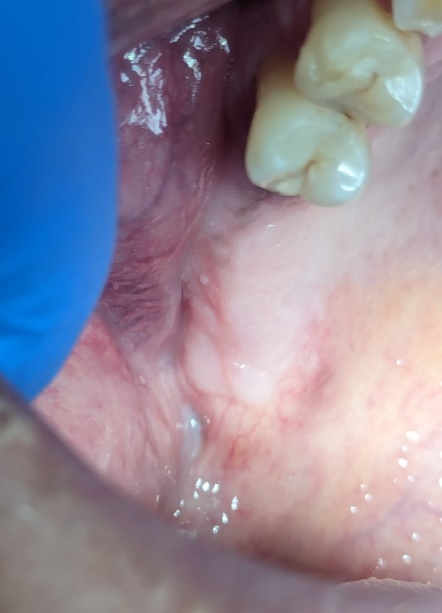

En la evaluación intraoral, se observó que el tejido blando del cuadrante uno presentaba una lesión de tipo inflamatoria de color grisácea-violácea vascularizada. Se realizaron radiografías periapicales de la zona en las cuales se observó un área mixta multiloculada, trabeculado óseo de forma irregular y con posible relación a la cortical del seno maxilar (Figura 1). Se solicitó Tomografía Computarizada de Haz Cónico (TCHC) y se realizó una biopsia incisional de la zona, abarcando un área de 1.5 x 1.5 cm.

Figura 1. Se observa (A) imagen clínica, radiografías periapicales de zona molares (B) y zona de premolares (C).